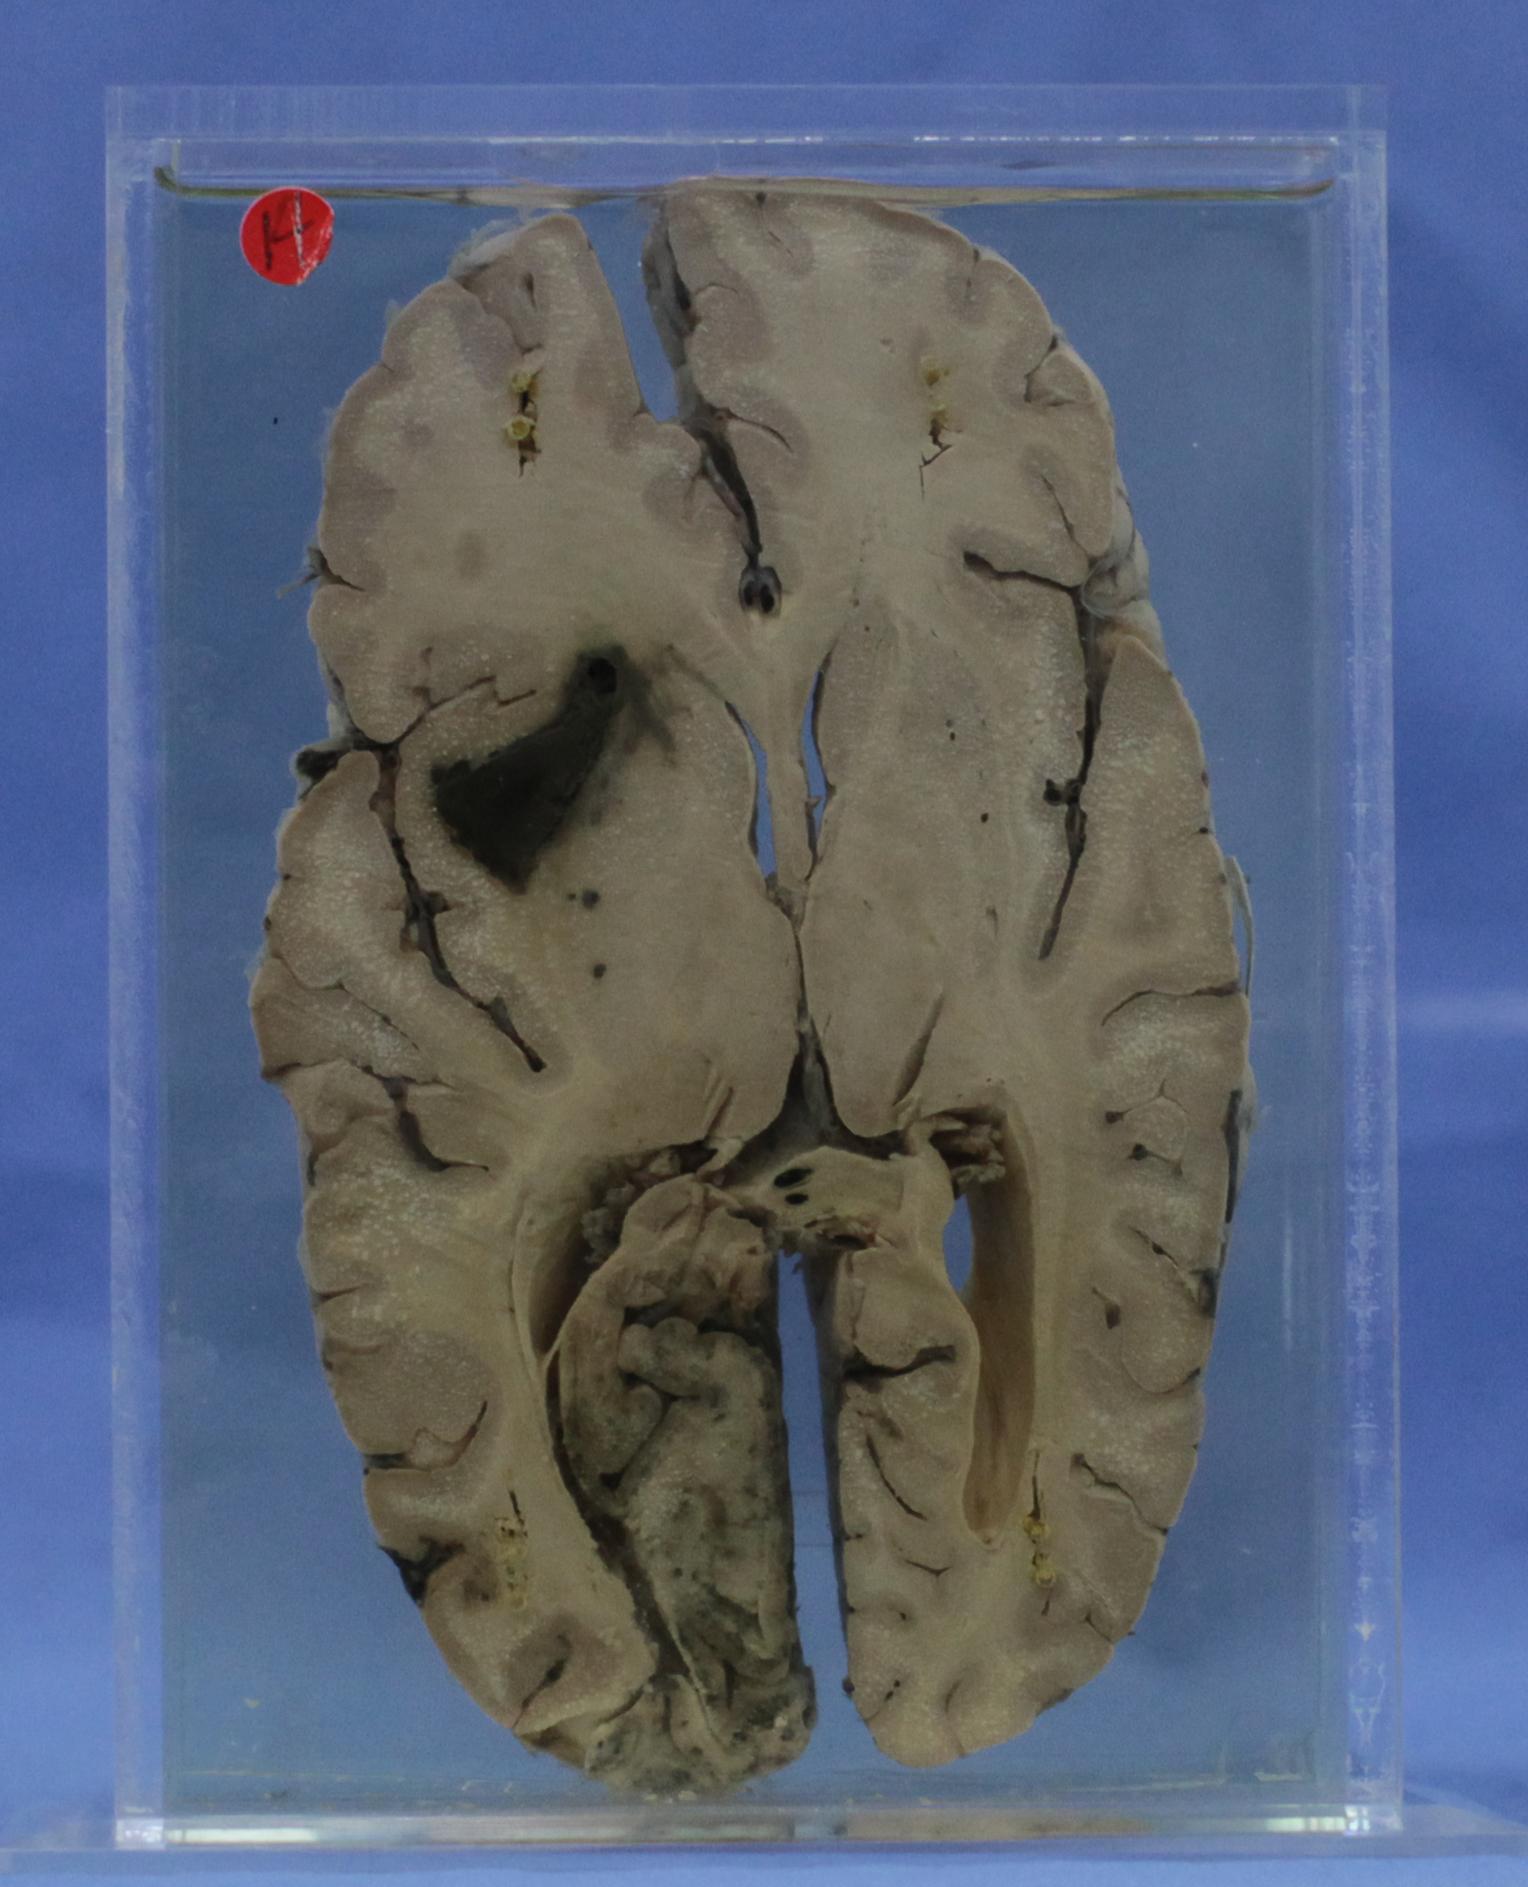

神经疾病-59-14. 左基底节及枕叶出血

大脑经基底节丘脑水平切面,左侧半球见基底节三角形新鲜出血,同侧侧脑室下脚受挤压变窄,同侧枕叶灰质可见大片足状出血。